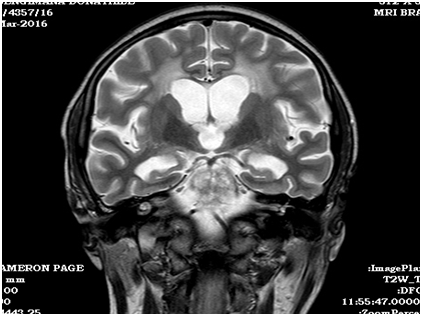

MRI revealed demyelinating lesions in the central pontine region consistent with osmotic demyelination syndrome (thin black arrow, Figure 1).  The 24-hour urine free cortisol was 415 mcg/dL (normal range 10-100 mcg/d). Overnight 8mg dexamethasone suppression test was 2.5 mcg/dL, which confirmed the diagnosis of Cushing disease. Her neuroleptic medications were held, and over the next two weeks she regained alertness and lucidity.

Figure 1A & B MRI revealed demyelinating lesions in the central pontine region.